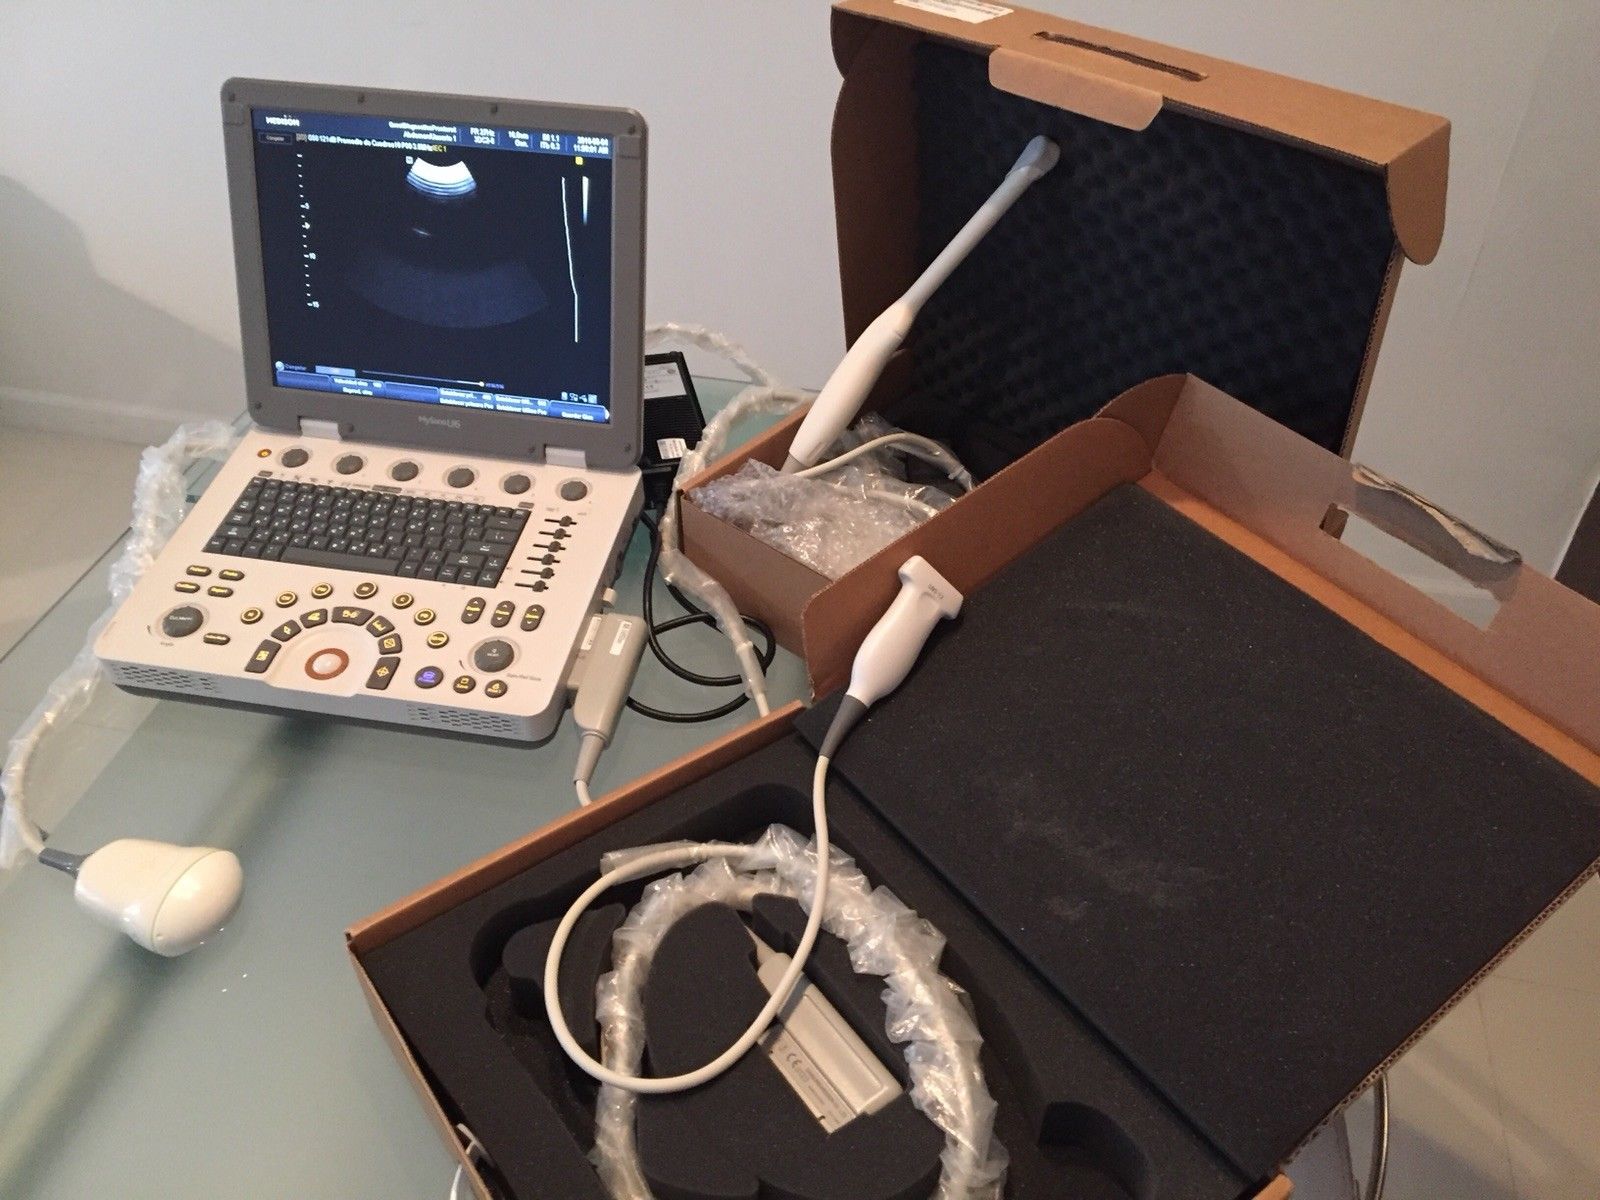

SAMSUNG HM70A PORTABLE ULTRASOUND WITH 2 PROBES

Sale price$ 11,150.88